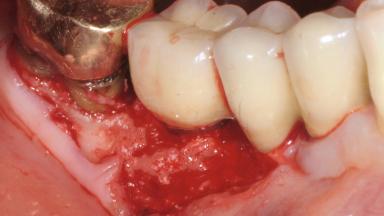

In this case, Mario Roccuzzo utilizes surgical bone regeneration treatment around implant 46 using a bone graft substitute and a connective tissue graft to resolve peri-implant inflammation, reduce the probing depths, and prevent further progression of disease.

A 58-year-old-male patient was referred in February 2007 for implant placement in the right mandibular molar area. Two tissue level implants were inserted at sites 44 and 46, respectively, to support a three-unit fixed dental prosthesis (FDP).